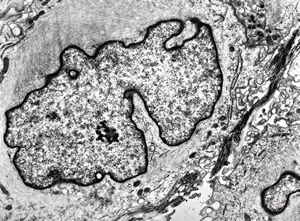

F, 57y. | mycosis fungoides … cerebriform nucleus of Sézary cell